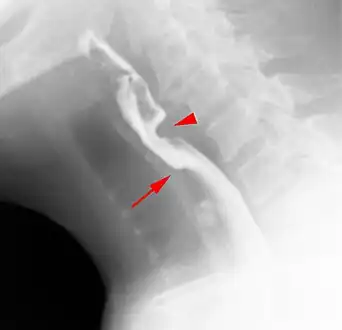

Web with "jet-phenomenon". Arrowhead on incomplete opening of the upper esophageal sphincter.